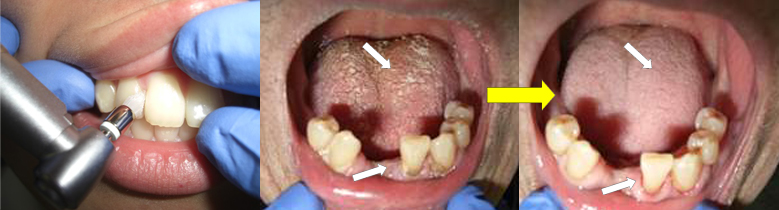

また、歯石などは全く自分で取ることができません。したがって、手術をしたり、抗がん剤や放射線治療を行う際には、特に体の抵抗力が弱りますから、自分で丁寧に歯磨きをするだけでは不十分です。必ず、歯科で専門的な口腔ケア(口腔内クリーニング、ブラッシング指導、虫歯や歯周炎の応急処置、義歯の調整など)を受けてください(図1)。

【図1】がんの治療が始まる前に、歯科でお口の中を徹底的にクリーニングしてもらいましょう。また、効果的なブラッシング法について指導を受けましょう。

歯科で専門的口腔ケアを受けると、口腔内の細菌数を大幅に減少させることができます(図2)。術前や術後に、専門的口腔ケアを受けて、口の中を可能な限り清潔に保つことができた人は、手術後の合併症(傷の感染や肺炎など)が少なく、結果的に入院日数が短縮できることが分かりました(図3、図4、図5)。